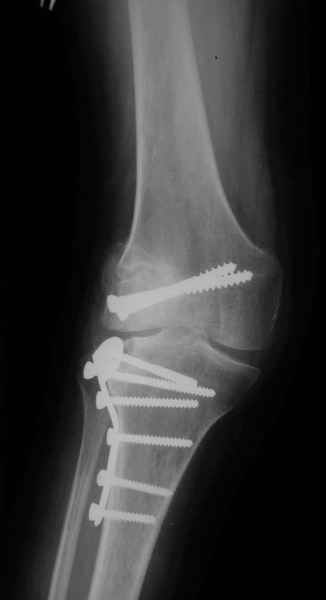

Уважаемый Евгений ! Спасибо за ответ, но мне представляется, что в нашем случае основной проблемой является не столько прогрессирующий вальгус конечности, сколько несросшийся перелом мыщелка бедра и дефект мыщелка большеберцой кости - вероятно первичная репозиция выполнялась без пластики.

Мы обсуждали вопрос первичного протезирования коленного сустава. На мой взгляд, данная больная не лучший кандидат для этого метода - большой дефект мыщелка бедра потребует первично использовать ревизионный протез. Обсуждался и вариант, аналогичный предложению В.Е.Казеннова - постепенное исправление деформации (вероятно с остеотомией голени) - большие сомнения в эффективности из-за наличия дефекта мыщелка б\б кости, расчет только на наличие в суставе массивнй рубцовой интерпонирующей "подушки".

На своем горьком опыте убедился, что синтезировать мыщелковые импрессионные внутрисуставные переломы б\б кости без костной пластики - дело неблагодарное, рецидивируе деформация, мыщелок всегда *проваливается*. Чистые split type переломы можно ограничиваться и одной только межфрагментарной компрессией.

Может стоит сначала добиться сращения наружного мыщелка бедра( костная пластика) и коррекции оси?

Мне представляется, что прогрессирующий вальгус и обусловлен несросшимся переломом мыщелка бедра (томограммы -зона межфрагментарного склерозирования), а циклические нагрузки на сустав во время ходьбы усугубляют ситуацию. Как вы думаете, в этой ситуации насколько вероятен риск развития аваскулярного некроза мыщелка бедра?